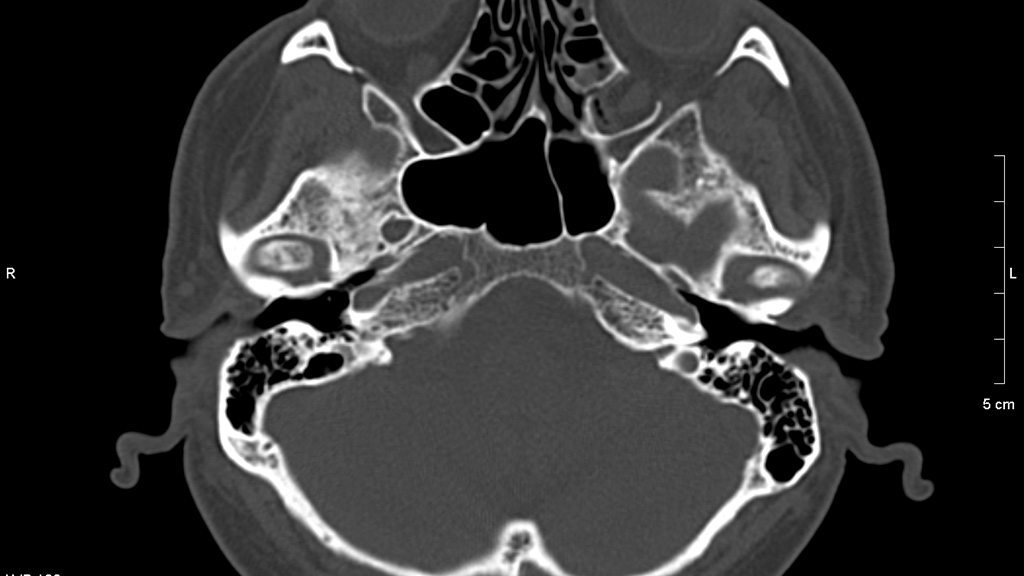

КТ в диагностике заболеваний височных костей

Докладчик: Коноплин Роман Константинович, врач-рентгенолог, член СРО "Ассоциация врачей МРТ и КТ-диагностики", .заведующий отделением лучевой диагностики "Клиника Эксперт Воронеж".